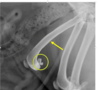

what is this?

Small kidney and abnormal ca

Was ist Das?

IVU

Mis-shapen – fibrotic

Small